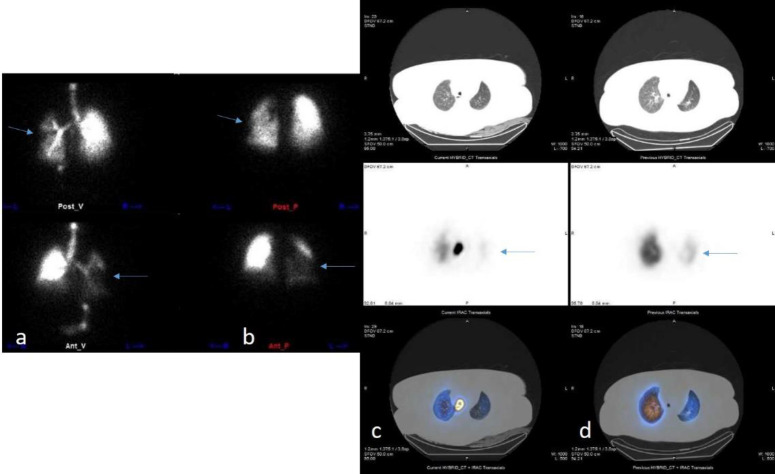

Methods: This was a cross-sectional study of patients with PCR-confirmed COVID-19 and suspected PE at a tertiary care hospital in 2020. They underwent ventilation/perfusion (V/Q) scintigraphy using single-photon emission computed tomography/computed tomography (SPECT/CT) and CT scans with or without contrast. Two blinded nuclear medicine physicians interpreted the images for PE and COVID-19. Clinical and laboratory data were extracted and analyzed.

Results: 96 patients with suspected PE and COVID-19 infection. The study excluded eight patients who could not undergo ventilation scans and confirmed PE in five patients with multiple mismatched V/Q defects on SPECT/CT. The study ruled out PE in 83 patients who had either regular perfusion scans, perfusion defects with COVID-19 features, or matched V/Q defects. The study found that the prevalence of PE was 5.68%, and the necessity of ventilation scans was 28.40% in this population.